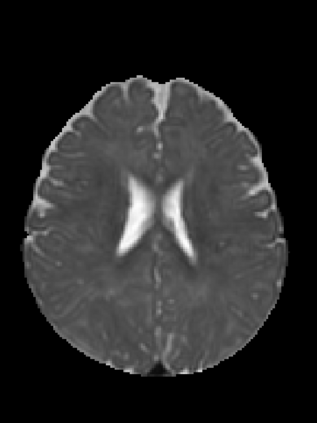

An important step in early brain development study is to perform automatic segmentation of infant brain magnetic resonance (MR) images into cerebrospinal fluid (CSF), gray matter (GM) and white matter (WM) regions. This task is especially challenging in the isointense stage (approximately 6-8 months of age) when GM and WM exhibit similar levels of intensities in MR images. Deep learning has shown its great promise in various image segmentation tasks. However, existing models do not have an efficient and effective way to aggregate global information. They also suffer from information loss during up-sampling operations. In this work, we address these problems by proposing a global aggregation block, which can be flexibly used for global information fusion. We build a novel model based on 3D U-Net to make fast and accurate voxel-wise dense prediction. We perform thorough experiments, and results indicate that our model outperforms previous best models significantly on 3D multimodality isointense infant brain MR image segmentation.